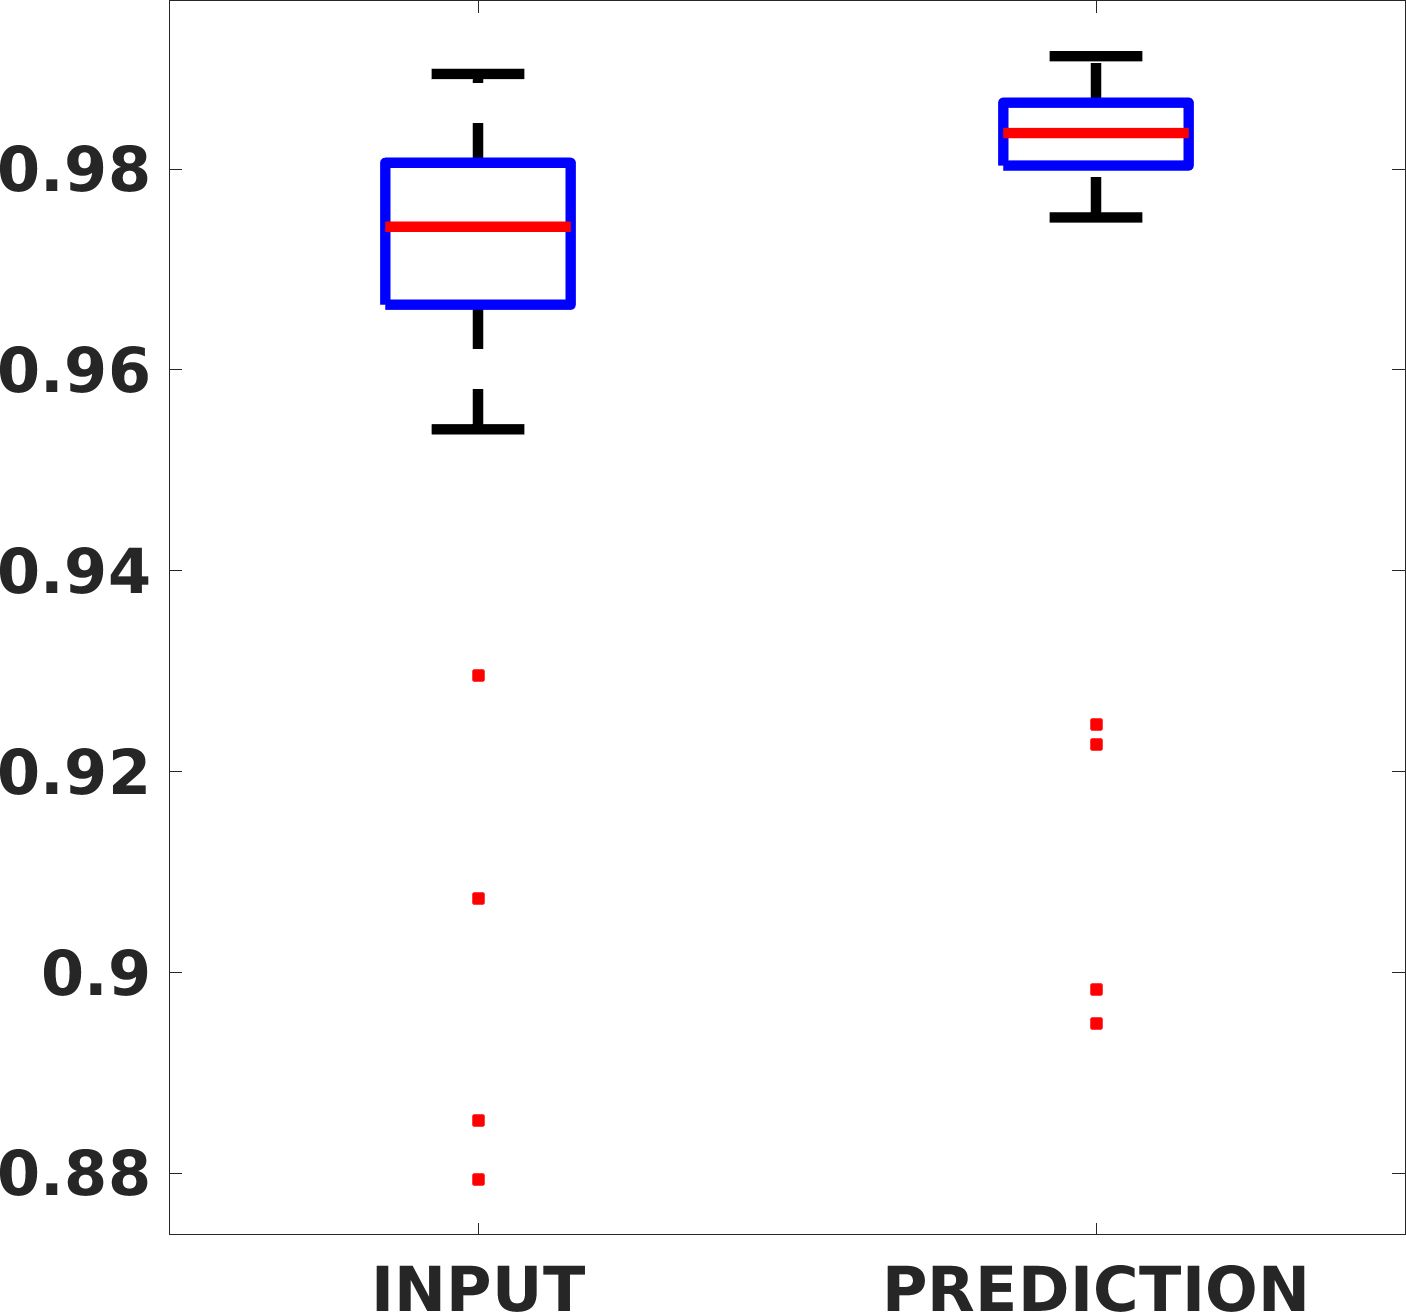

Fig. 8 shows the box plot of the SSIM (a-b-c, left) and MAE (a-b-c, right) quantitative metrics, as performed for PSNR metric. Also, these metrics show that our method improves the results of Cubic convolution both in terms of average value and variability. For example, the SSIM median value improves of on obstetric 4X images and the MAE median value improves of on cardiac 2X images.

Fig. 17 (left) shows the box plot of the quantitative metrics, comparing the target images with the prediction and the Cubic convolution, respectively. The PSNR metric is computed on a data set of 200 images, belonging to the same district, and with the same up-sampling factor. Analysing the obstetric anatomical district and concerning the corresponding raw images (Fig. 7 (a, left)), the denoising allows the network to significantly improve the results of the up-sampling and the prediction. In particular, comparing the target images with the predicted images, the median PSNR value of obstetric 2X denoised images is 51.8, compared to the median PSNR value of obstetric 2X raw images which is 36.9.

Fig. 17 (right) shows the histogram of the absolute value of the error with respect to the target, of the prediction and Cubic convolution respectively. This result shows that our framework increase of and (2X and 4X, respectively) the number of pixels where the prediction error is lower than 5, which is very similar to the target when visually analysing the images, and improved with respect to the learning framework applied to raw images. According to Fig. 18, our method improves the accuracy of Cubic convolution. For example, the SSIM increases of on cardiac 2X and the MAE increases of on abdominal 4X.